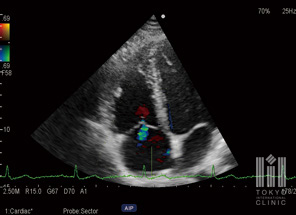

心臓超音波検査

心臓が動いている様子を映し出し、壁の動きや弁の開閉の状態を調べます